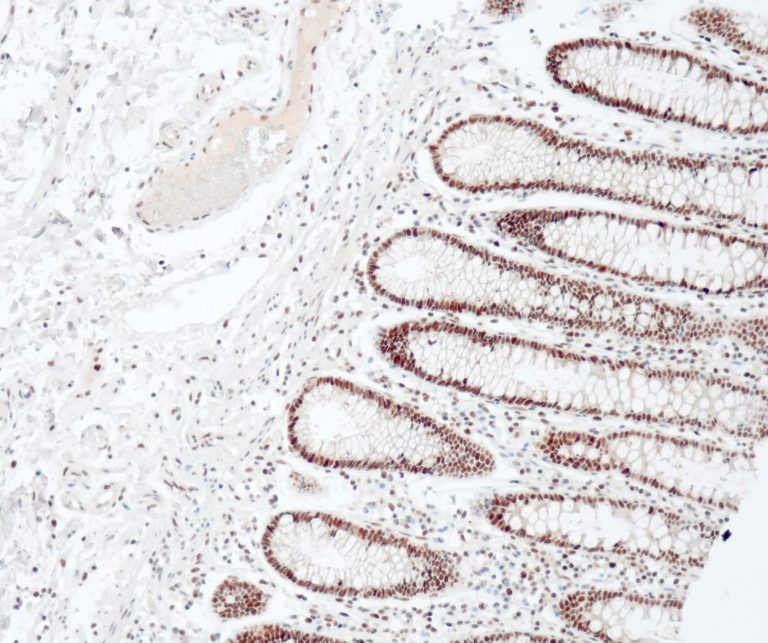

Gastrointestinal (GI) Pathology

General Marker